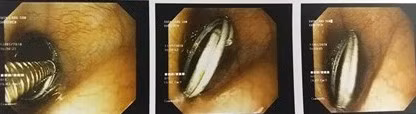

Tiến hành chụp X quang, các bác sĩ phát hiện một vòng kim loại đường kính khoảng 2 cm ở 1/3 dưới thực quản. Bệnh nhi đã được các bác sĩ tiến hành gây mê, nội soi gắp dị vật. Sau 10 phút, dị vật được lấy ra an toàn. Hiện tại, tình trạng bệnh nhi đã ổn định.

| Hình ảnh vòng kim loại trong thực quản bệnh nhi. |